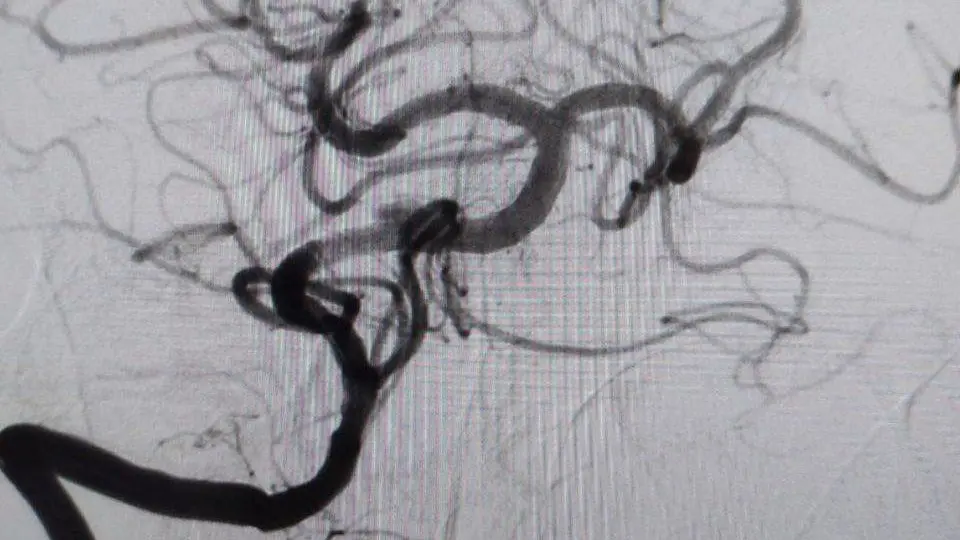

«Пациент перенес атеротромбоз основной артерии, питающей ключевые зоны головного мозга – состояние высокой опасности с серьезным прогнозом. Мы действовали четко и успели провести операцию вовремя, что подарило нам счастливый исход», – с оптимизмом отметила глава медицинского учреждения Элеонора Тулякова.